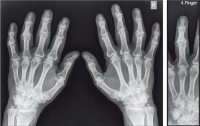

Abbildung 2a-b: 11 Monate nach Therapiestart